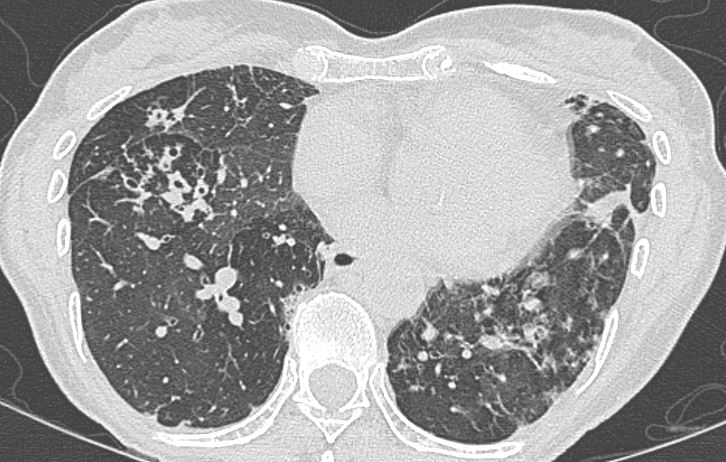

Bronchiectasis and goals of antibiotic treatment – thinking it through

The setting – patients with bronchiectasis (including those with cystic fibrosis) have impaired respiratory secretion clearance and a vastly different lower respiratory flora (microbiome) than patients with normal lungs. They are frequently colonised with conventional respiratory species such as Haemophilus influenzae and Moraxella catarrhalis, Staphylococcus aureus, a diverse range of Gram negative bacteria and even fungi. Colonisation/infection with non-tuberculous […]